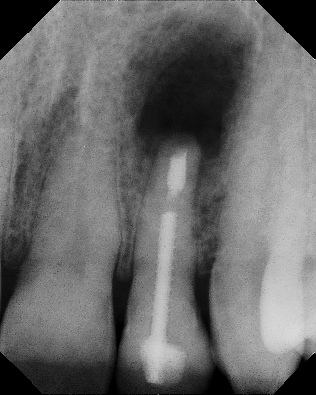

COMPLICATED ANATOMY LARGE LESIONS CALCIFIED CANALS PERFORATION / RESORPTION SEPARATED INSTRUMENTS SURGICAL CASES RETREATMENT / pOST REMOVAL OPEN APICES ACCESS THRU CROWNS Root Canal Case Portfolio

Apicoectomy - Surgical Root Canal Pre-op (post trauma) Coronal segments obturated Apical segments surgically removed 3 years